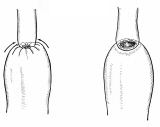

壁細胞。休止状態と分泌状態

どこかの国際学会でスライドに使っていただいたようです。確か一枚目を描くのに5時間、二枚目が3時間かかりました。